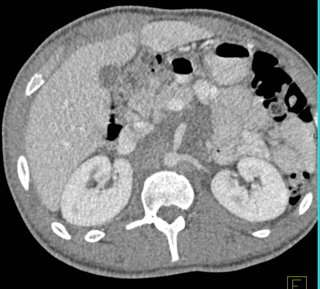

The best diagnosis in this case is?

lymphoma

neurofibromatosis

metastatic adenocarcinoma

MAI infection